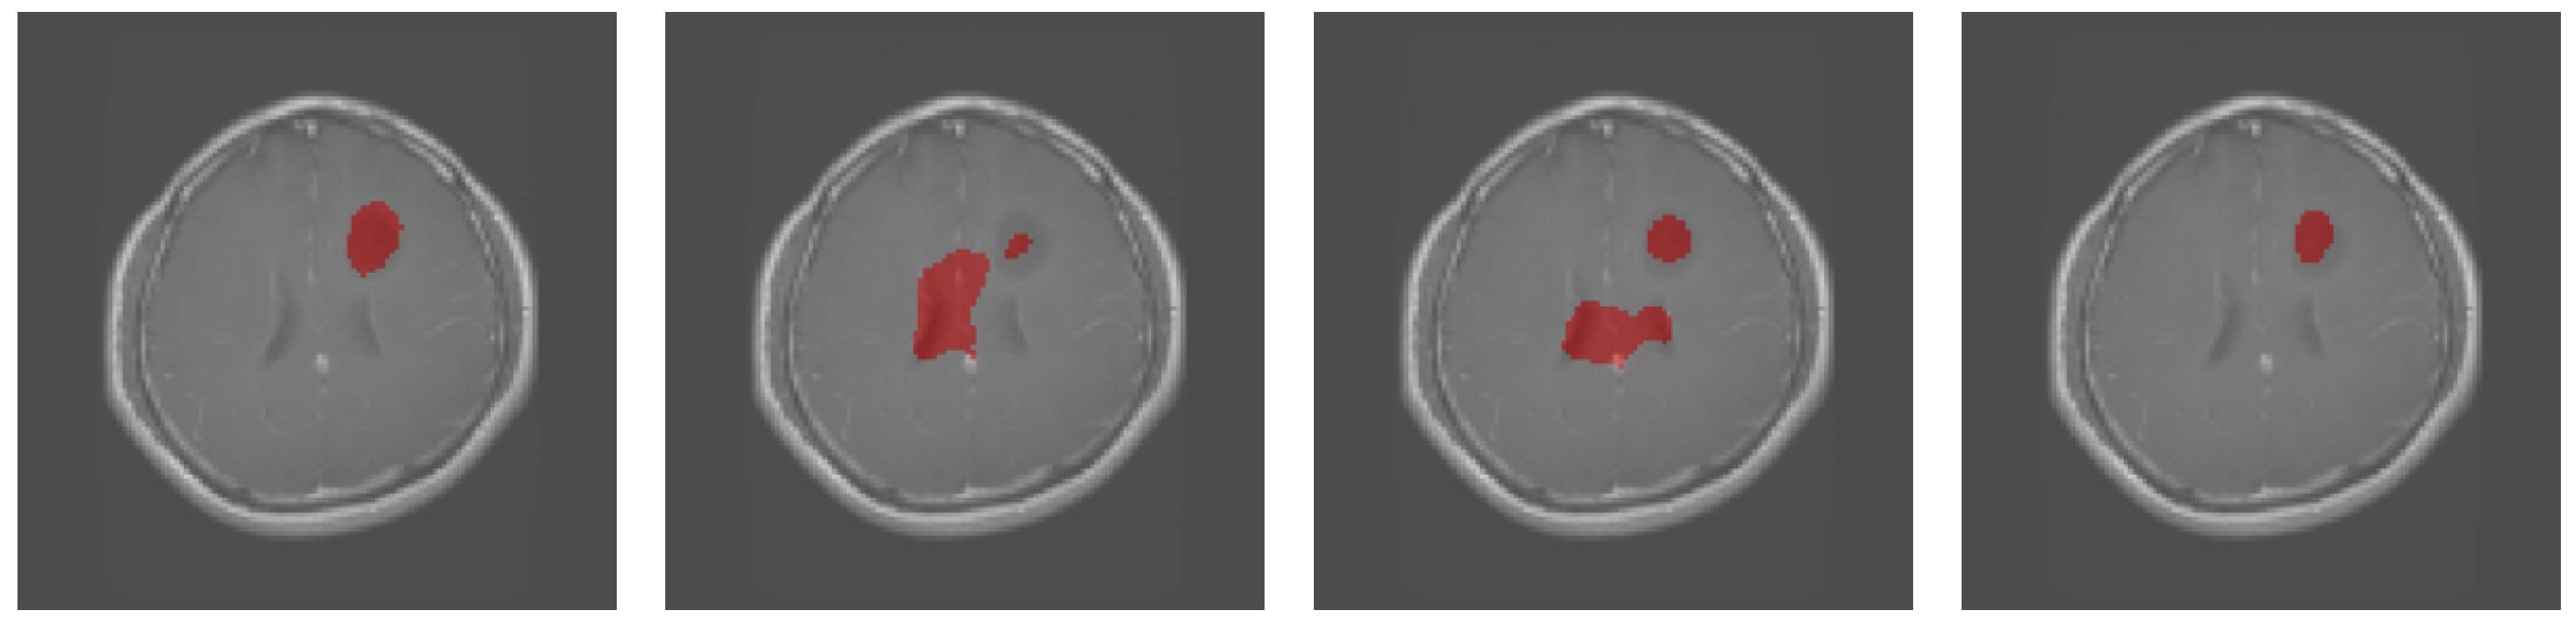

3.1. Results Obtained on the Brain MRI Dataset

| Dice | TPR | TNR | HD95 | |

|---|---|---|---|---|

| U-Net | 54.35% | 45.23% | 99.80% | 9.22 |

| UNet++ | 56.45% | 48.35% | 99.76% | 8.06 |

| Att-UNet | 58.06% | 46.87% | 99.86% | 8.35 |

| Focus-UNet | 48.59% | 37.34% | 99.85% | 9.43 |

| SAB-Net | 61.83% | 55.15% | 99.78% | 8.06 |